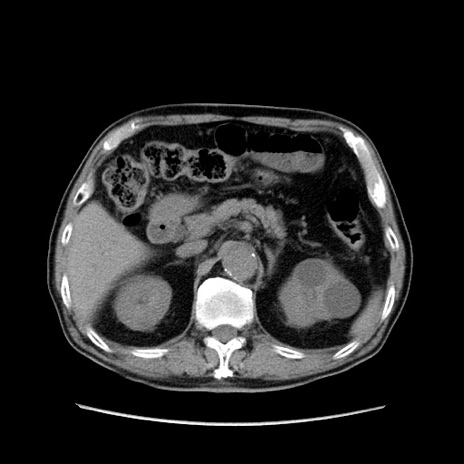

症例24(横断像)

【症例】80歳代男性

【主訴】左側腹部痛、嘔吐

【現病歴】本日早朝より左腹部に痛みあり。昼頃嘔吐認めたため、救急要請。

【既往歴】直腸癌(Mile手術)、胆摘

【身体所見】意識清明、BT 35.9℃、BP 221/93mmHg、SpO2 97%(RA) 、腹部:左ストーマ周囲に限局性の腹部膨隆あり。 膨隆部自発痛・圧痛あり・軟。

【データ】WBC 7700、CRP 0.09